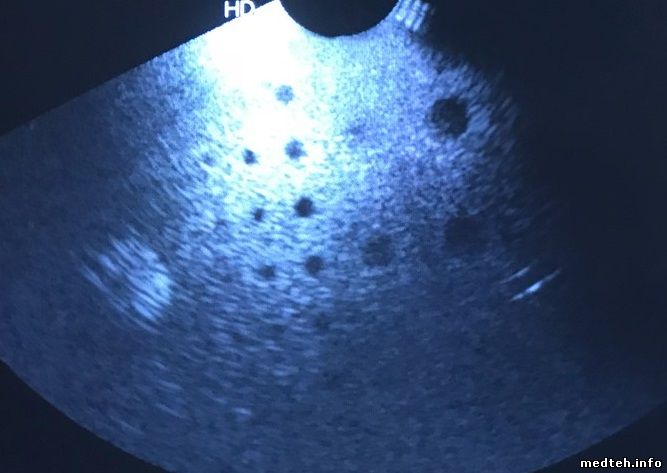

Подскажите, что может быть двоятся и искажаются объекты в определенных секторах датчика вагинального, какие соображения? Прикладываю фото сухого датчика и с дефектом, изображение фантома.

7521158.jpg (29.0 Kb) · 1084120.jpg (53.0 Kb) · 0850773.jpg (37.7 Kb)